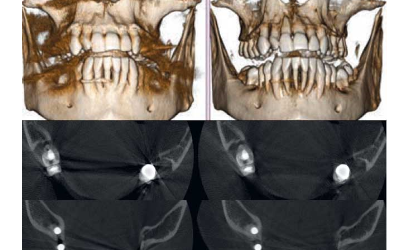

3D SMART

La fonction intelligente 3D SMART (Streak Metal Artifacts Reduction Technology) permet de réduire les artéfacts métalliques sur les images 3D, avec une procédure complètement automatique. Rendez vos images volumétriques toujours exploitables, même en présence d’implants et de restaurations en amalgame.

Planification implantaire avancée

Définissez la position de l’implant directement sur le modèle 3D, combinez-le avec les données STL provenant de scanners intra-oraux, et déterminez le projet prothétique définitif. Avec les instruments de planification implantaire avancée, vous pourrez opérer en toute sécurité, grâce aux informations précises sur la quantité d’os et la distance par rapport aux structures anatomiques avoisinantes, comme le canal mandibulaire, en définissant une distance minimale de sécurité.

La fonction du logiciel de calcul du volume de soulèvement du sinus maxillaire permet de déterminer l’intervention à l’avance et d’opérer en toute sécurité. Il est en outre possible de tracer des lignes directement sur le modèle virtuel du patient en évaluant les rapports morphologiques sur le rendu 3D.